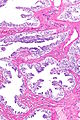

Adenomatous hyperplasia of the rete testis

Adenomatous hyperplasia of the rete testis. H&E stain. | |

| LM | epithelium with tubulopapillary or cribriform architecture separated by small amount of stroma |

Adenomatous hyperplasia of the rete testis (abbreviated AHRT), also rete testis adenomatous hyperplasia, is a rare benign lesion of the rete testis that may be confused with malignancy.[1][2]

- Epithelium with tubulopapillary or cribriform architecture separated by small amount of stroma.